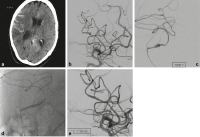

Abbildung 2a-f: Die 45-jährige Patientin hatte über einige Tage Nackenschmerzen, dann Vernichtungskopfschmerz. Im CT (a) zeigte sich eine präpontine Blutansammlung. Im MRT (b) waren ältere und frischere Blutabbauprodukte nachweisbar. Die Angiographie (c) bestätigte ein fusiformes Aneurysma des rechten proximalen intraduralen V4-Segmentes mit vorgeschalteter Stenose. Ein Mikrokatheter wurde durch das Aneurysma in das distale V4-Segment eingeführt und darüber ein flusskorrigierender Stent (p64 3,5 × 21 mm, Phenox, Bochum, Deutschland) vorgebracht. Ein zweiter Mikrokatheter wurde im Aneurysma positioniert und darüber eine Coil vorbereitet (d). Während der flusskorrigierende Stent freigesetzt wurde, erhielt die Patientin die gewichtsadaptierte Initialdosis Eptifibatid (Intergrilin®, Glaxo Smith Kline, München, Deutschland) über den Führungskatheter. Gleichzeitig wurden über den zweiten Mikrokatheter Coils in das Aneurysma eingebracht und dann 500 mg Aspirin (Aspirin i.v., Bayer AG, Leverkusen, Deutschland) intravenös gegeben (e). Die intravenöse Erhaltungsdosis Eptifibatid wurde für 24h weitergeführt. Im Anschluss wurde für 12 Monate eine duale Thrombozytenaggregationshemmung mit ASS 100 mg/d und Clopidogrel 75 mg/d durchgeführt. Die Angiographiekontrolle nach einem Jahr (f) zeigte das behandelte V4-Segment mit normalem Kaliber, das Aneurysma war ausgeschaltet, es bestand kein neurologisches Defizit.